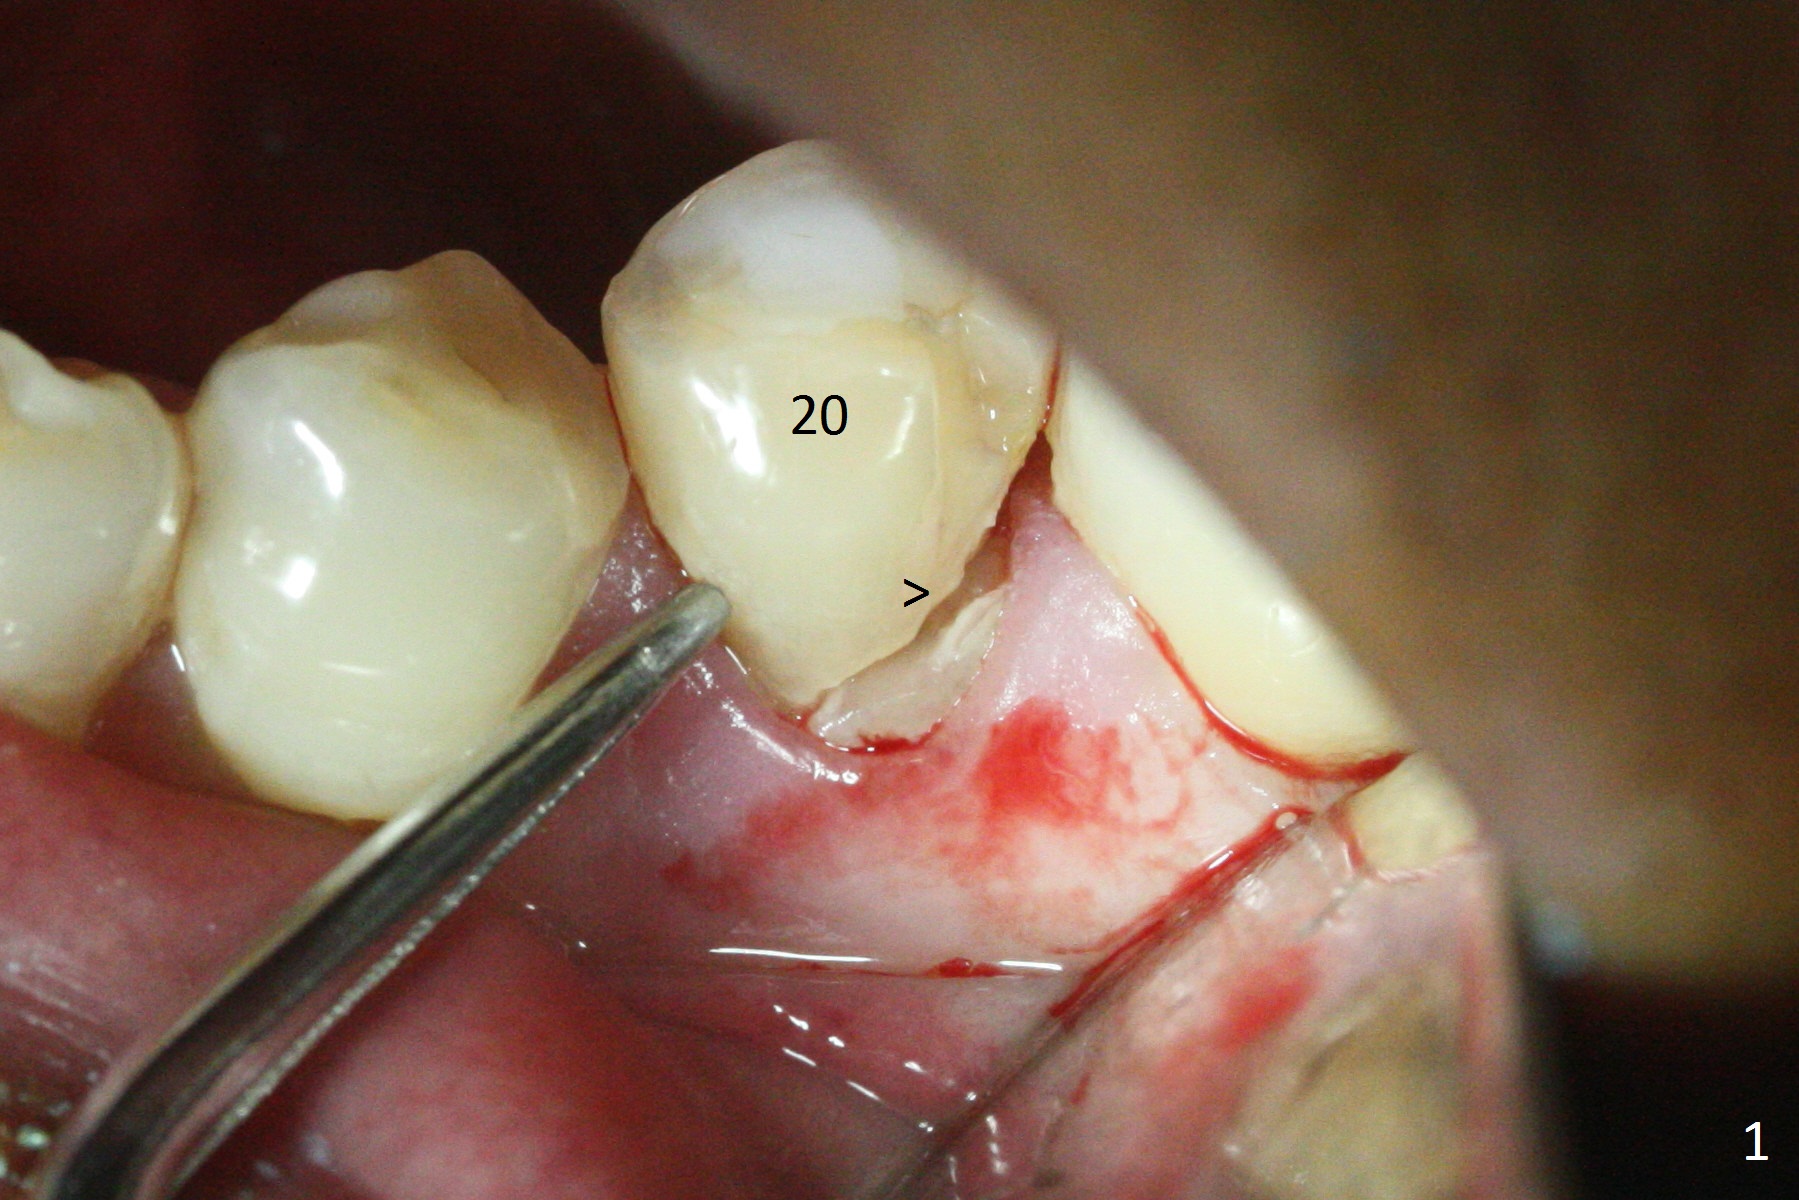

Extraction of the lower left 2nd premolar with vertical fracture (Fig.1,2 >) is easy because of peri-radicular radiolucency.  The apical end of the osteotomy is not shown with a 2 mm pilot drill (Fig.3) or a 3.8x18 mm implant (Fig.4) in place.  It appears that the implant is not placed deep enough.  Following 3-4 more turns of the implant and placement of a 5.5x4(3) mm abutment (Fig.5 A), allograft is placed (*).  A postop panoramic X-ray is taken (Fig.6); the osteotomy could have been deepened to reduce the possibility of periimplantitis.  Retrospectively, the panoramic X-ray should be taken after use of the pilot drill. The bone around the implant appears to have regenerated 4 months postop (Fig.7,8).  Bone density appears to continue increasing 9 months postop (i.e., 4.5 months post cementation, Fig.9).  Bone loss is minimal 2 years post cementation (Fig.10).